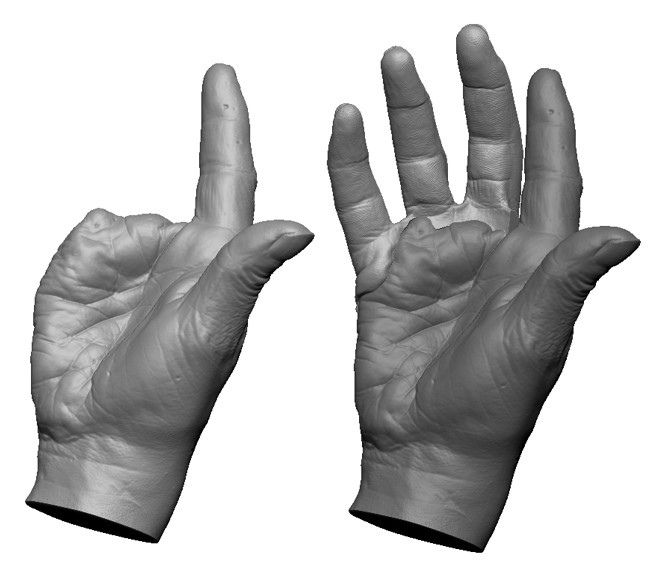

The Master of Science program in Clinical Anaplastology (CA) provides students with knowledge to succeed as clinicians providing facial, ocular (eye), and non-weight bearing somatic (body) prostheses, as well as designing 3D patient-matched models, surgical templates and other 3D printed clinical models.

- Examples of the work created